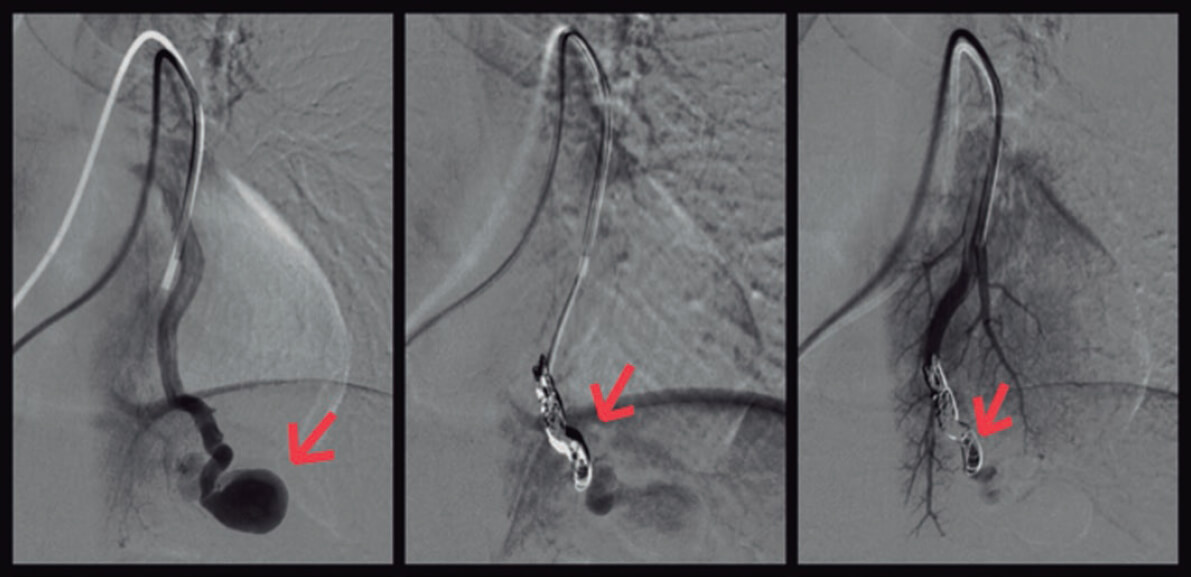

El servicio de intervencionismo procedió al cierre de las fístulas mediante microcateterización selectiva de las arterias segmentarias aferentes a ellas y embolización con coils (figura 3, flechas).

Figura 3.